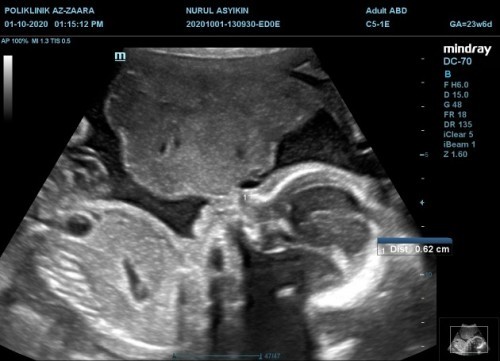

Detail Scan 24w

Alhamdulillah dah buat detail scan smuanya normal. Uri kat atas kepala baby pun dah pusing bawah. Air ketuban pun smue ok. Alhamdulillh mudah2an baby sihat sampai di lahirkan nnt.. Amiin..

clearnya gambar scan sis. saya pun buat dekat az zahra time 24w, tak clear macamni pun 😅

la ye ke. smue gmbr yg dktr tu bg kat saya smue clear..